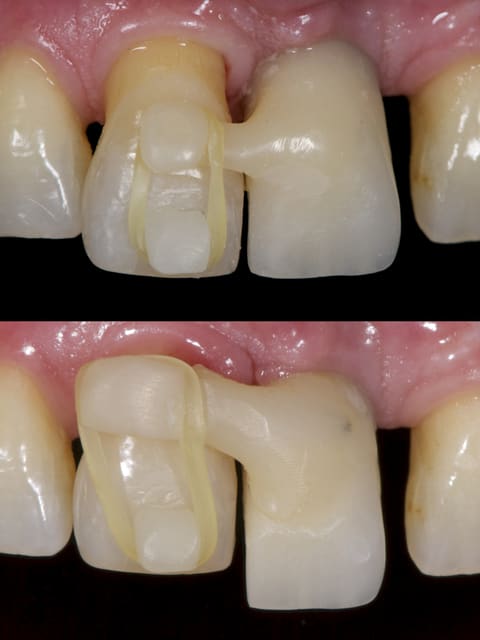

05/08/2014 à 11h23

Comme demandé en MP voici le contrôle 10 mois après la pose.

C'est acceptable je pense. Ce traitement a ses limite bien sûr mais peut être une indication voire une alternative dans certains cas spécifiques comme celui-ci.

Au passage, qui connait le nom que l'on donne à cette collerette de GA que l'on voit sur 13-12-11-22-23, j'ai oublié.

A omtjjz - Eugenol

1 zf3owi - Eugenol

Img 0812 mvp6i0 - Eugenol

jeamba

05/08/2014 à 20h20

Je ne sais pas si tu as réellement ingressé car quad je regarde ta radio du départ et celle que tu viens de mettre, ton apex arrive pratiquement au même niveau de spire, à savoir au niveau de la troisième spire en partant de l'apex de l'implant. Il y a quelque chose qui m'échappe.